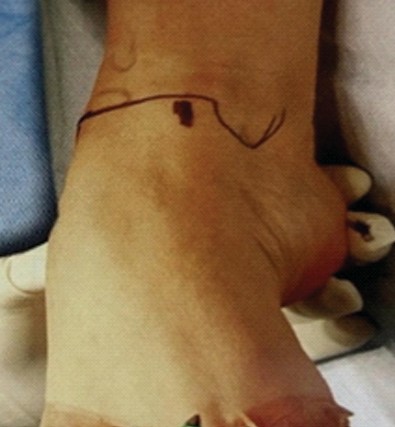

The anterior or posterior two-portal approach is selected based on the location of the osteochondral lesion of the talus (OLT). Patients undergoing the anterior approach were positioned supine position. An anteromedial and anterolateral two-portal approach was made (Fig. 1 and 2). Just medial to the tibialis anterior tendon helps define the anteromedial portal and the anterolateral portal just laterals to the peroneus tertius tendon. Arthroscopic microfracture is a reparative cartilage procedure performed under direct visualization to address OLTs (Fig. 3). For reference, Figure 4 shows osteochondral lesion over the talus.

Figure 1: Anteromedial portal.

Figure 2: Anterolateral portal.